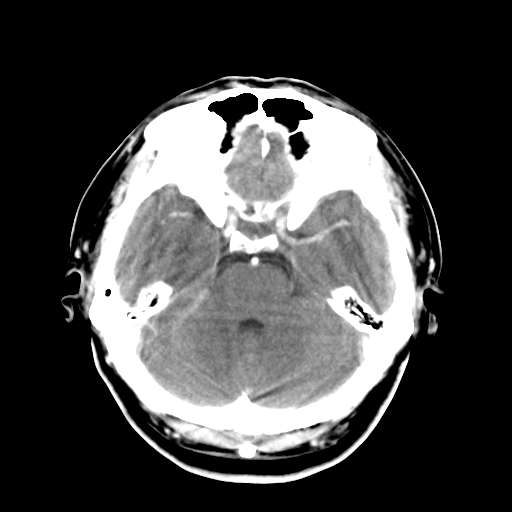

标题: CT16447B:(续)增强扫描图像。

患者今日做ct增强检查,现补传增强扫描图像。

松果体钙癍增大,无其他改变,定不了性

一般认为大于1cm为异常。